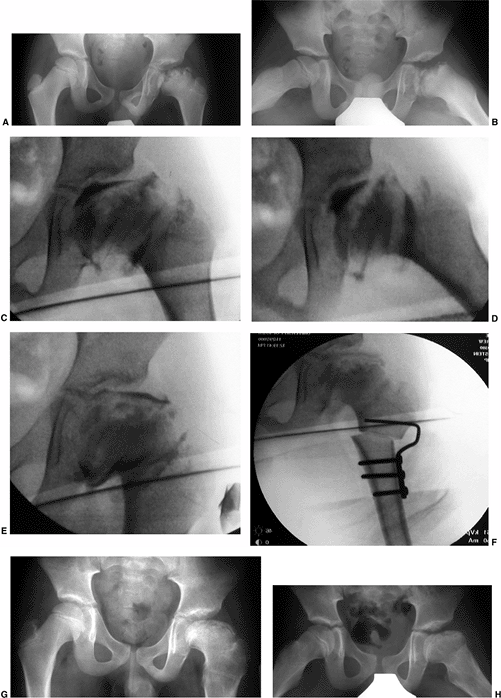

Figure 25.2

A girl, 4 years and 8 months of age, was treated for left hip Perthes disease (late fragmentation phase) beginning in January 1983. Anteroposterior (right, A–I) and Lauenstein (see pg. 1044, A–I) views of the right hip at different stages, January 1983 to December 1987. A: View of the right hip at the time of initial presentation with no signs of involvement (January 1983). B: Early involvement, patient still asymptomatic (September 1983). C–F: Progressive healing of the right femoral epiphysis at May 1984 (C), August 1984 (D), May 1985 (E), and November 1985 (F). G: Femoral head was completely healed by December 1986. H: Recurrent changes in the density of the femoral head and a subchondral fracture that involves less than 50% of the head (Catterall group 2) was seen in June 1987. I: Complete involvement of the ossific nucleus (Catterall group 4) with diffuse metaphyseal reaction and cysts in December 1987. (From Martinez AG, Weinstein SL. Recurrent Legg-Calvé-Perthes’ disease: case report and review of the literature. J Bone Joint Surg Am 1991;73:1081.) |